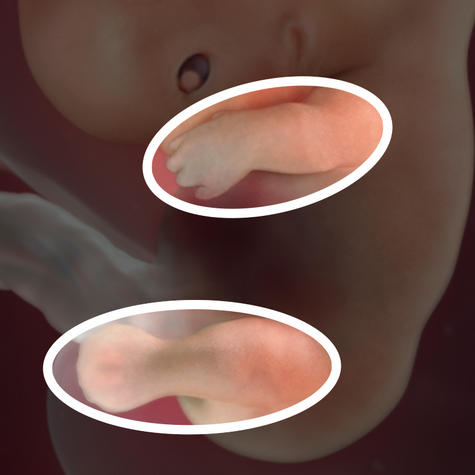

Пальчики вашої дитини злегка збільшені, так як на них розвиваються чутливі області

У дитини з'являються все основні суглоби - плечі, стегна, зап'ястя, щиколотки, коліна, лікті

Особа плода округляється і поступово починає бути схожим на обличчя людини. Очі переміщаються на своє природне місце розташування, ближче до носа. Вже можна розрізнити губи, ніс з ніздрями і вуха. Пальці на руках подовжуються, перетинки між ними поступово зникають. На ногах починається формування пальців і нігтів.

Дев'ятий тиждень вагітності - це час активного розвитку м'язової системи плода. Дитина вже може згинати і розгинати верхні і нижні кінцівки.